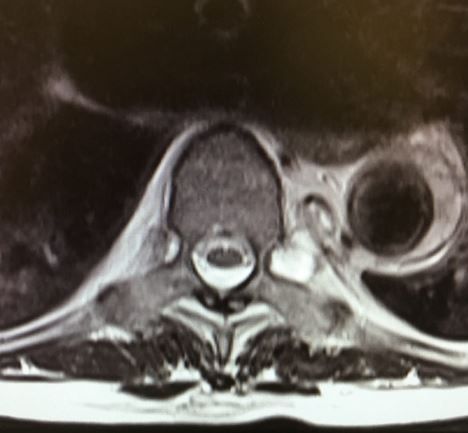

Initial diagnostic testing: An MRI of the spine is performed assess for nerve root compression with special concern for a possible spinal epidural hematoma (image).